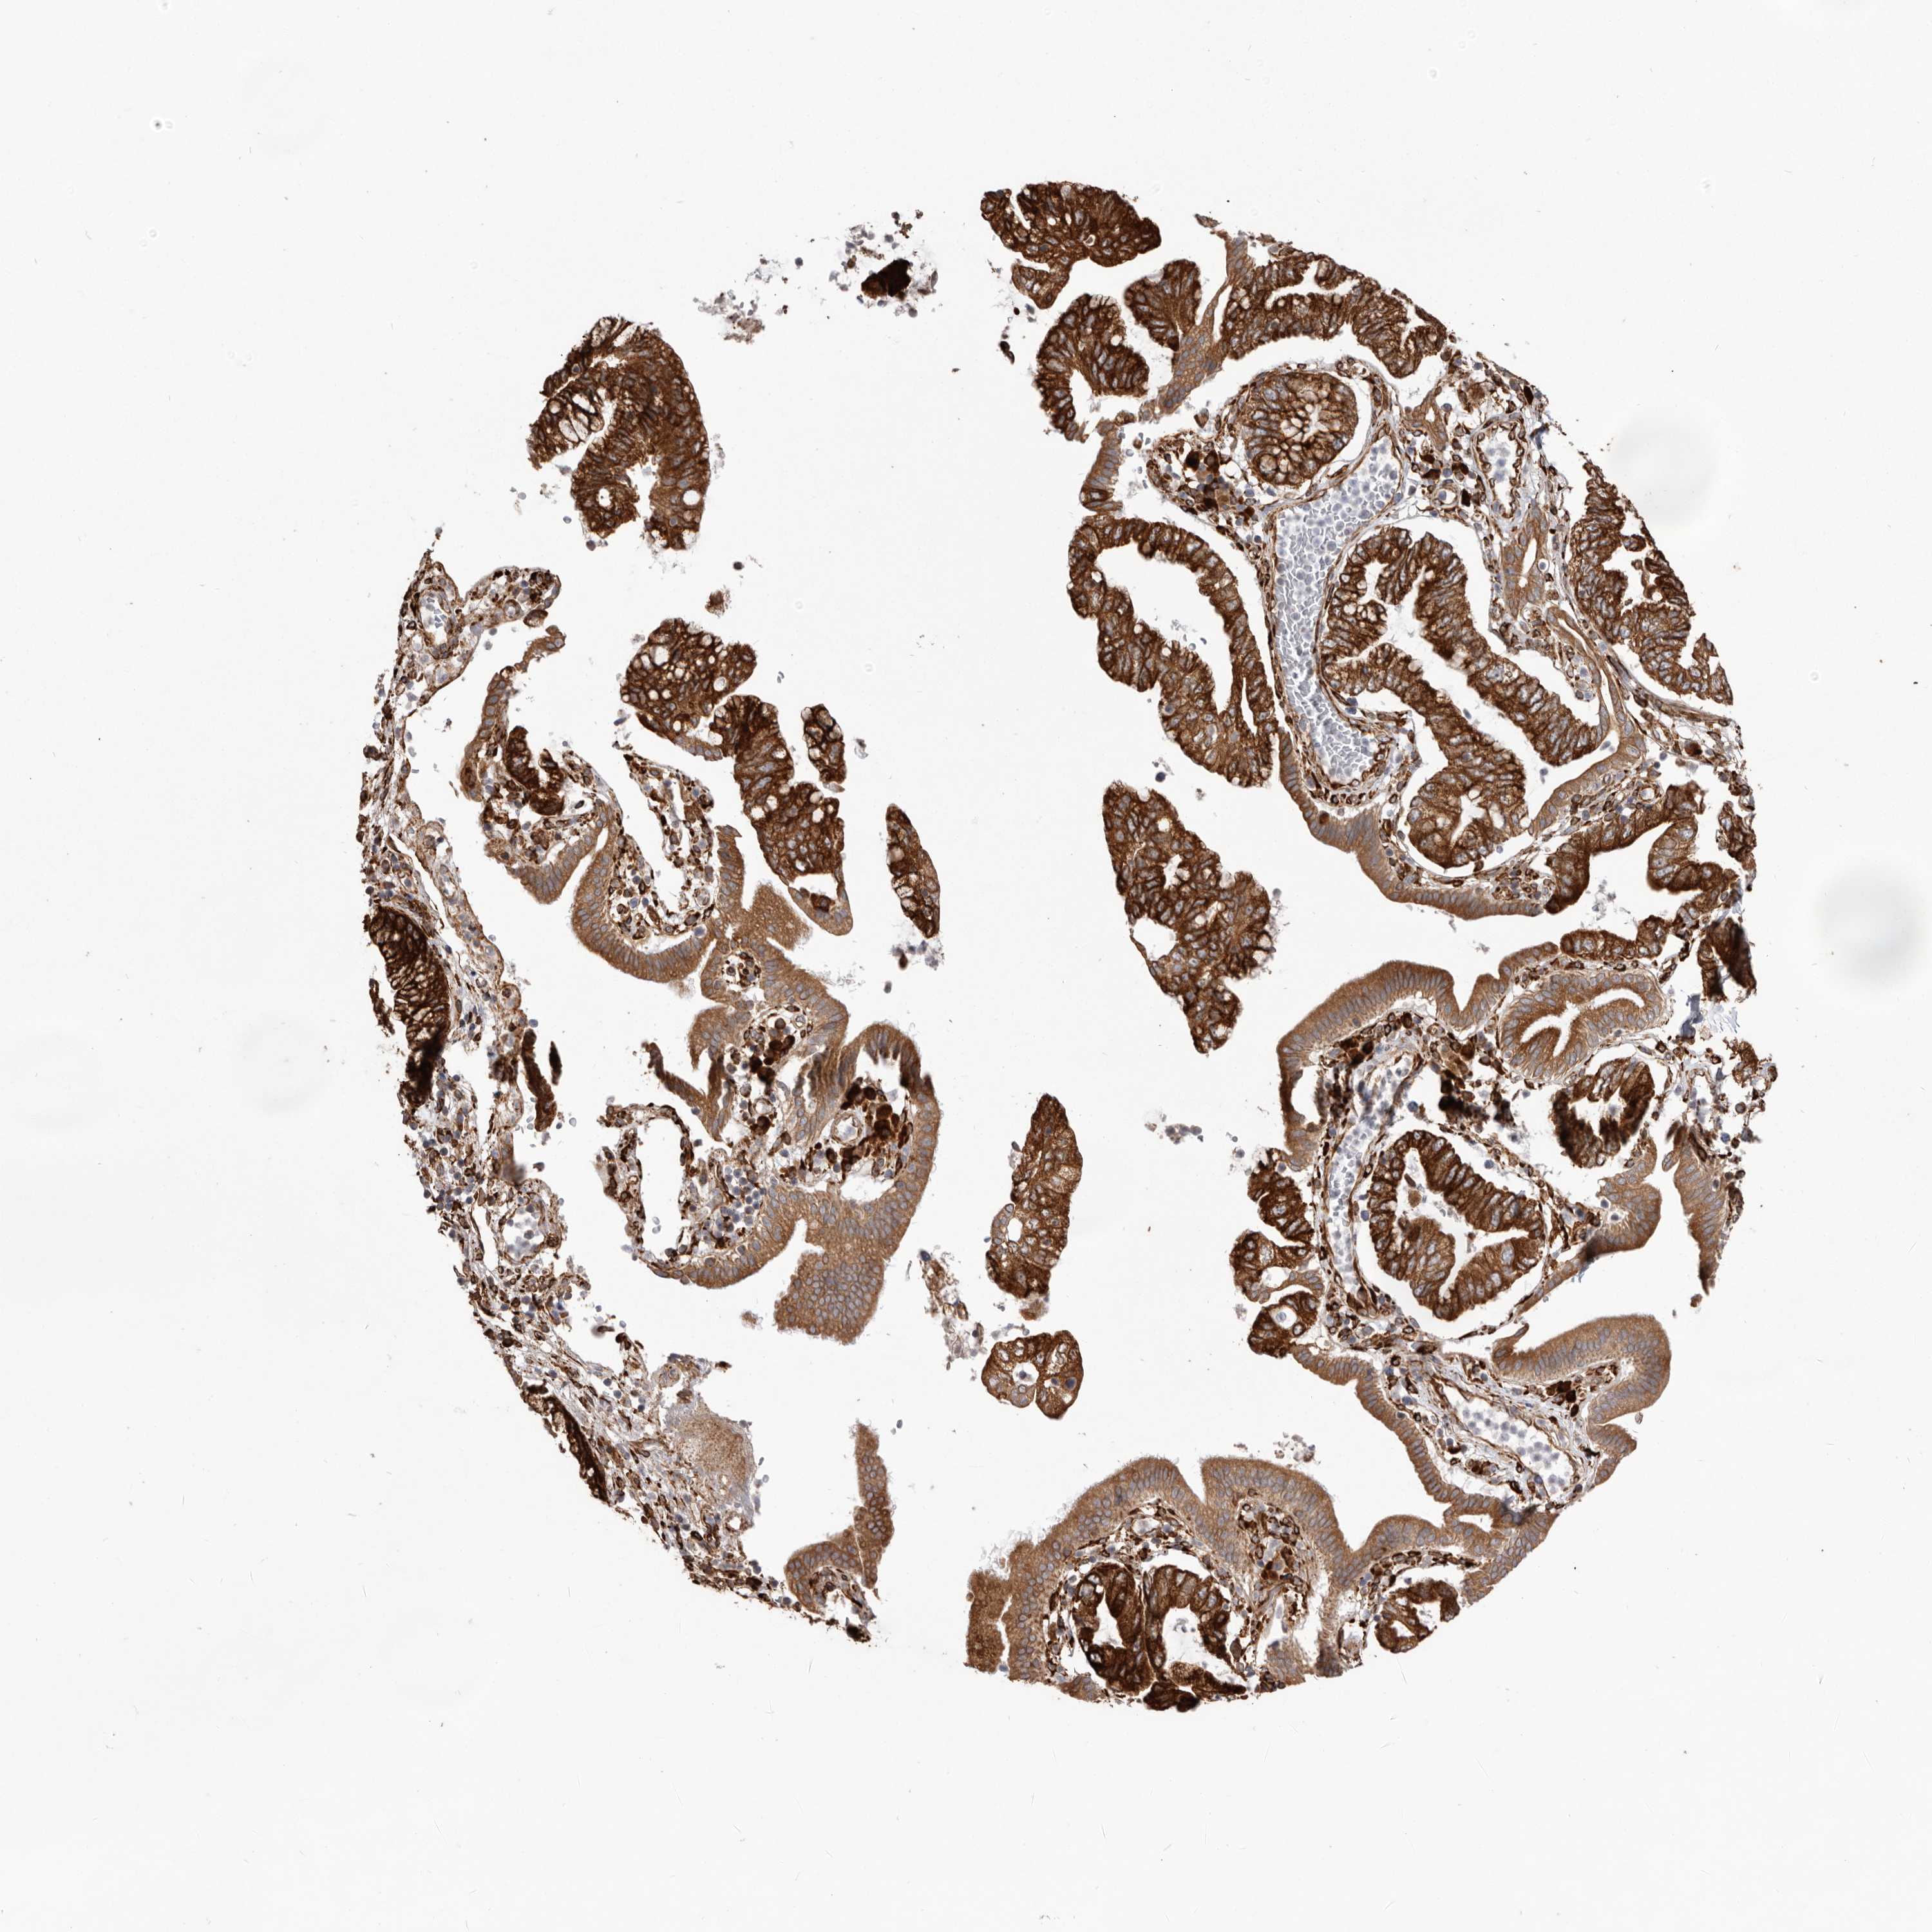

PANCREATIC CANCER - Protein expressioni

A mouse-over function shows sample information and annotation data. Click on an image to view it in a full screen mode. Samples can be filtered based on level of antibody staining by selecting one or several of the following categories: high, medium, low and not detected. The assay and annotation is described here.

Note that samples used for immunohistochemistry by the Human Protein Atlas do not correspond to samples in the TCGA dataset.

Antibody stainingi

Antibody staining in the annotated cell types in the current human tissue is reported as not detected, low, medium, or high, based on conventional immunohistochemistry profiling in selected tissues. This score is based on the combination of the staining intensity and fraction of stained cells.

Each image is clickable and will lead to virtual microscopy that enables deeper exploration of all samples and also displays staining intensity scores, fraction scores and subcellular localization as well as patient and tissue information for each sample.

Antibody HPA028177

Antibody HPA028180

Antibody HPA028182

Staining

High

Medium

Low

Not detected

Intensity

Strong

Moderate

Weak

Negative

Quantity

>75%

75%-25%

<25%

None

Location

Nuclear

Cytoplasmic/membranous

Cytoplasmic/membranous,nuclear

Adenocarcinoma, NOS